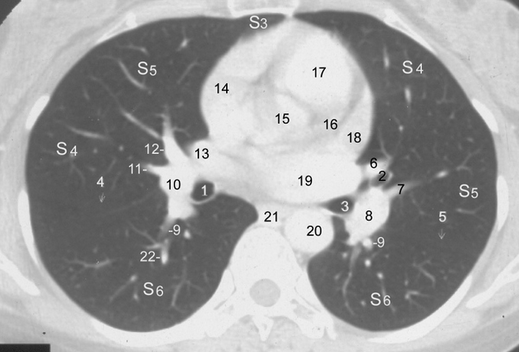

而要完成这一工作,首先需要非常清楚地知道正常的人体解剖结构及断层解剖结构(影像图片大多是断层图片),而且还要了解正常的人体变异(是的,即使正常的人体结构,很多人也有变异,不能误判是异常),之后要清楚地知道异常的组织结构,这就需要时间和经验的积累,所谓见多识广。